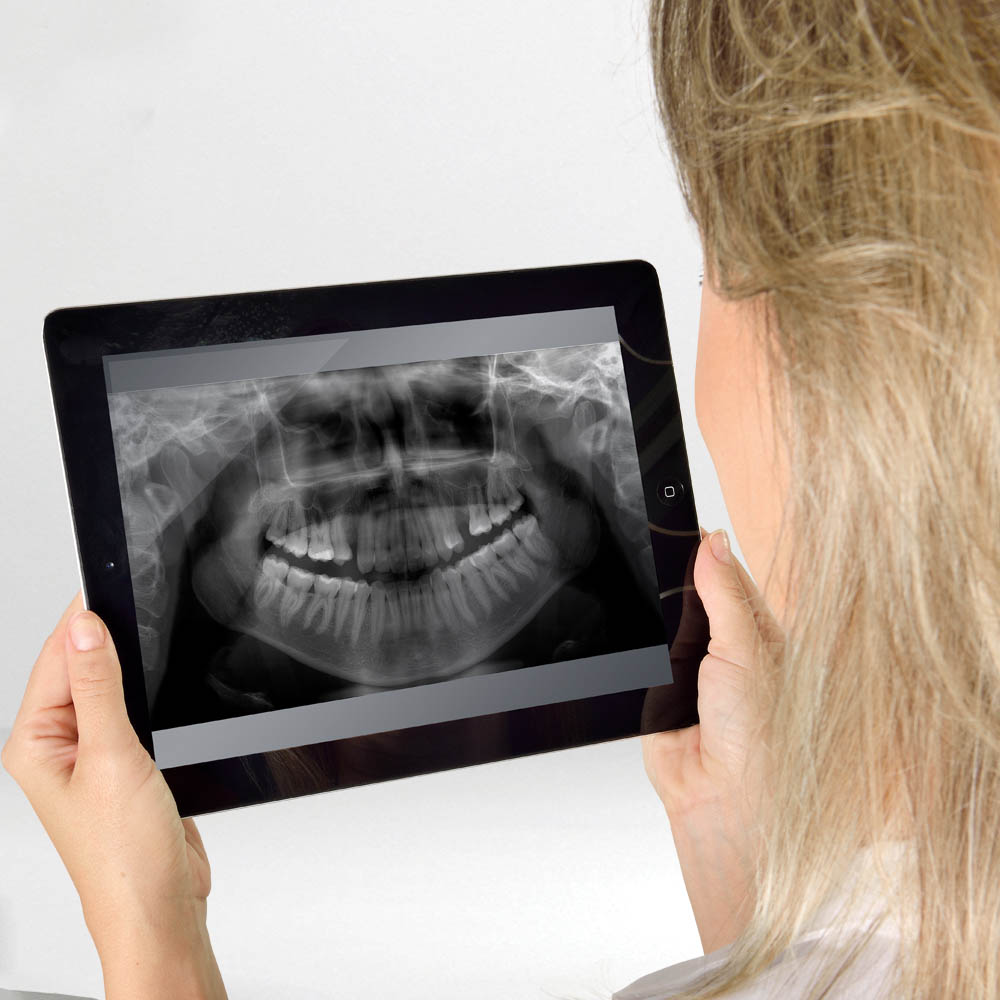

Imágenes instantáneas en el iPad

El software Eagle permite que las tomas radiográficas sean enviadas de forma instantánea por wirelles a toda la clínica y se puede acceder a ellas con total seguridad por cualquier iPad, tablet o notebook. Gana tiempo, comparte imágenes por la rede y tamién impresiona a sus clientes con la tecnología de su clínica.